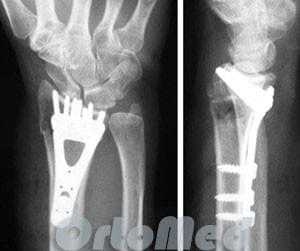

Открытая репозиция перелома лучевой кости

Открытая репозиция накостный остеосинтез пластиной и винтами. Операция включает в себя хирургический разрез, доступ к сломанной кости аккуратно отводя сухожилия, сосуды и нервы, мобилизацию костных отломков, устранение смещения и фиксация в правильном положении. Сломанные кости фиксируются титановыми пластинами, ввиду этого пациенту разрешается ранняя разработка движений в лучезапястном суставе.

До операции:

После операции:

После операции

Открытая репозиция накостный остеосинтез пластиной и винтами. Операция включает в себя хирургический разрез, доступ к сломанной кости аккуратно отводя сухожилия, сосуды и нервы, мобилизацию костных отломков, устранение смещения и фиксация в правильном положении. Ход операции продемонстрирован на видео:

Сломанные кости фиксируются титановыми пластинами, ввиду этого пациенту разрешается ранняя разработка движений в лучезапястном суставе. К тому же не обязательно нашение гипсовой лонгеты, т.к. металлоконструкция удерживает отломки в парвильном положении достаточно жестко, что исключает смещение при движениях.